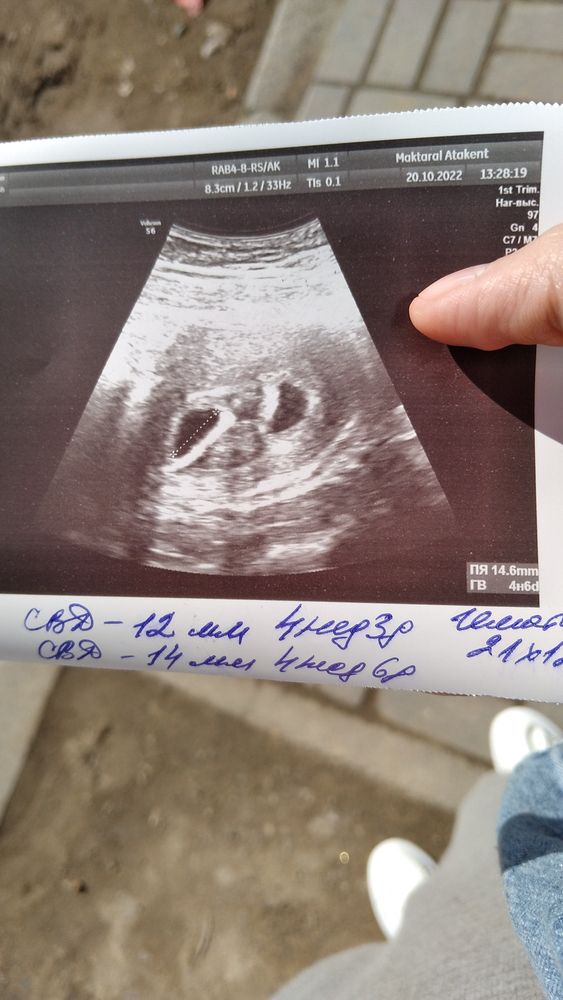

Изображение Вот так выглядит ди ди двойня

Ди ди определяют как видите на моем снимке, и в 4 недель и в 5,6,7 и т.д. А моно моно или моно ди определяется чуть позже, имею ввиду перегородка между ними есть или нет и т.д. Ди ди это два разных плодных яйца, два амниона, два хориона, две плаценты, два желточных мешочка. То есть 2 сперматазоида оплодотворили 2 яйцеклетки (они могут созреть как в одном яичнике, так и в двух и оплодотворение может быть в разное время например один эмбрион прикрепился сегодня, а второй через несколько дней и т.п.) могут быть разнополыми и не похожи друг на друга. А моно ди или моно моно это один сперматозоид оплодотвоиил одну яйцеклетку и в итоге они поделились внутри. Тут много чудес очень )))